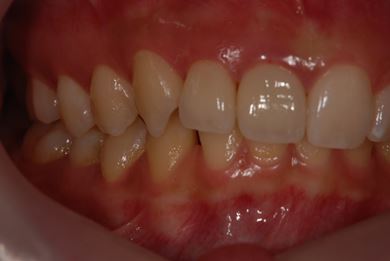

| 性別/年齢 | 女性 / 21歳 | ||||||||||||||||||||||||||||||||

| 主訴 | 歯の変色、欠けた部分を治したい。 | ||||||||||||||||||||||||||||||||

| 治療方針 | 上前歯を根管治療後、オールセラミッククラウンにて審美的回復を行う。 | ||||||||||||||||||||||||||||||||

| 治療内容 | オールセラミッククラウン2本(オールセラミック用土台2本) | ||||||||||||||||||||||||||||||||